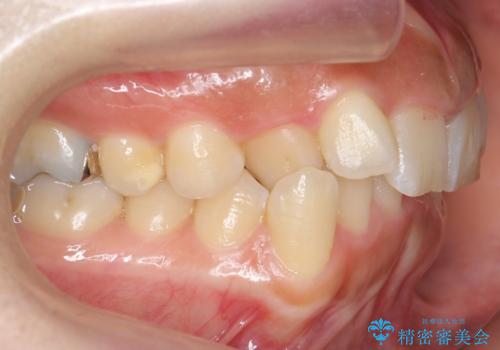

前歯のがたつき ガミースマイルの改善

- 前歯のがたつきとガミースマイルの改善を希望して来院。

ガミーは非常に軽度でひどくはなかったのですが、改善を強く希望されていました。

上の前歯をひっぱりあげて目立たなくするために、上の前歯のワイヤー部分矯正を行い、ミニスクリューからわずかに引っ張り上げました。

また、右上の犬歯の反対咬合についてもワイヤー矯正で短期間で改善することができました。

前歯の過蓋咬合についても改善しています。